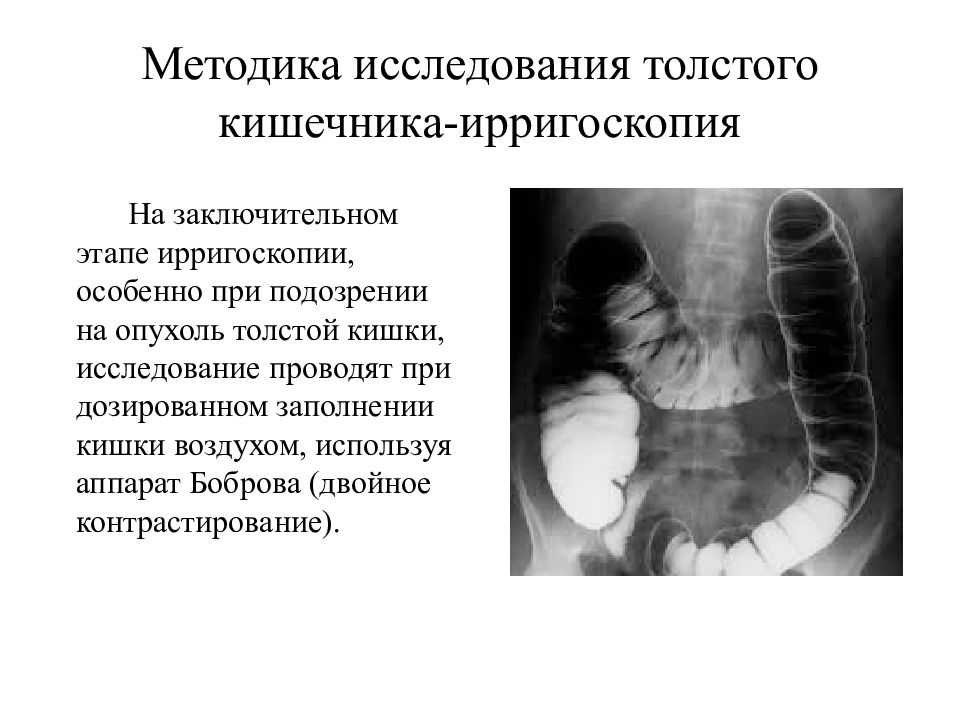

Подготовка к ирригоскопии: необходимые препараты